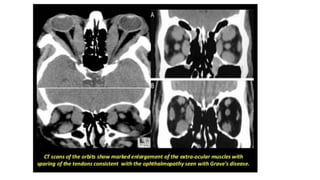

Grave’s disease

• Associated with optalmopathy

Ultrasonographic features of Grave’s disease

• Hyper vascularity

• Diffuse coarse thyroid echo

texture

• Diffuse gland enlargement